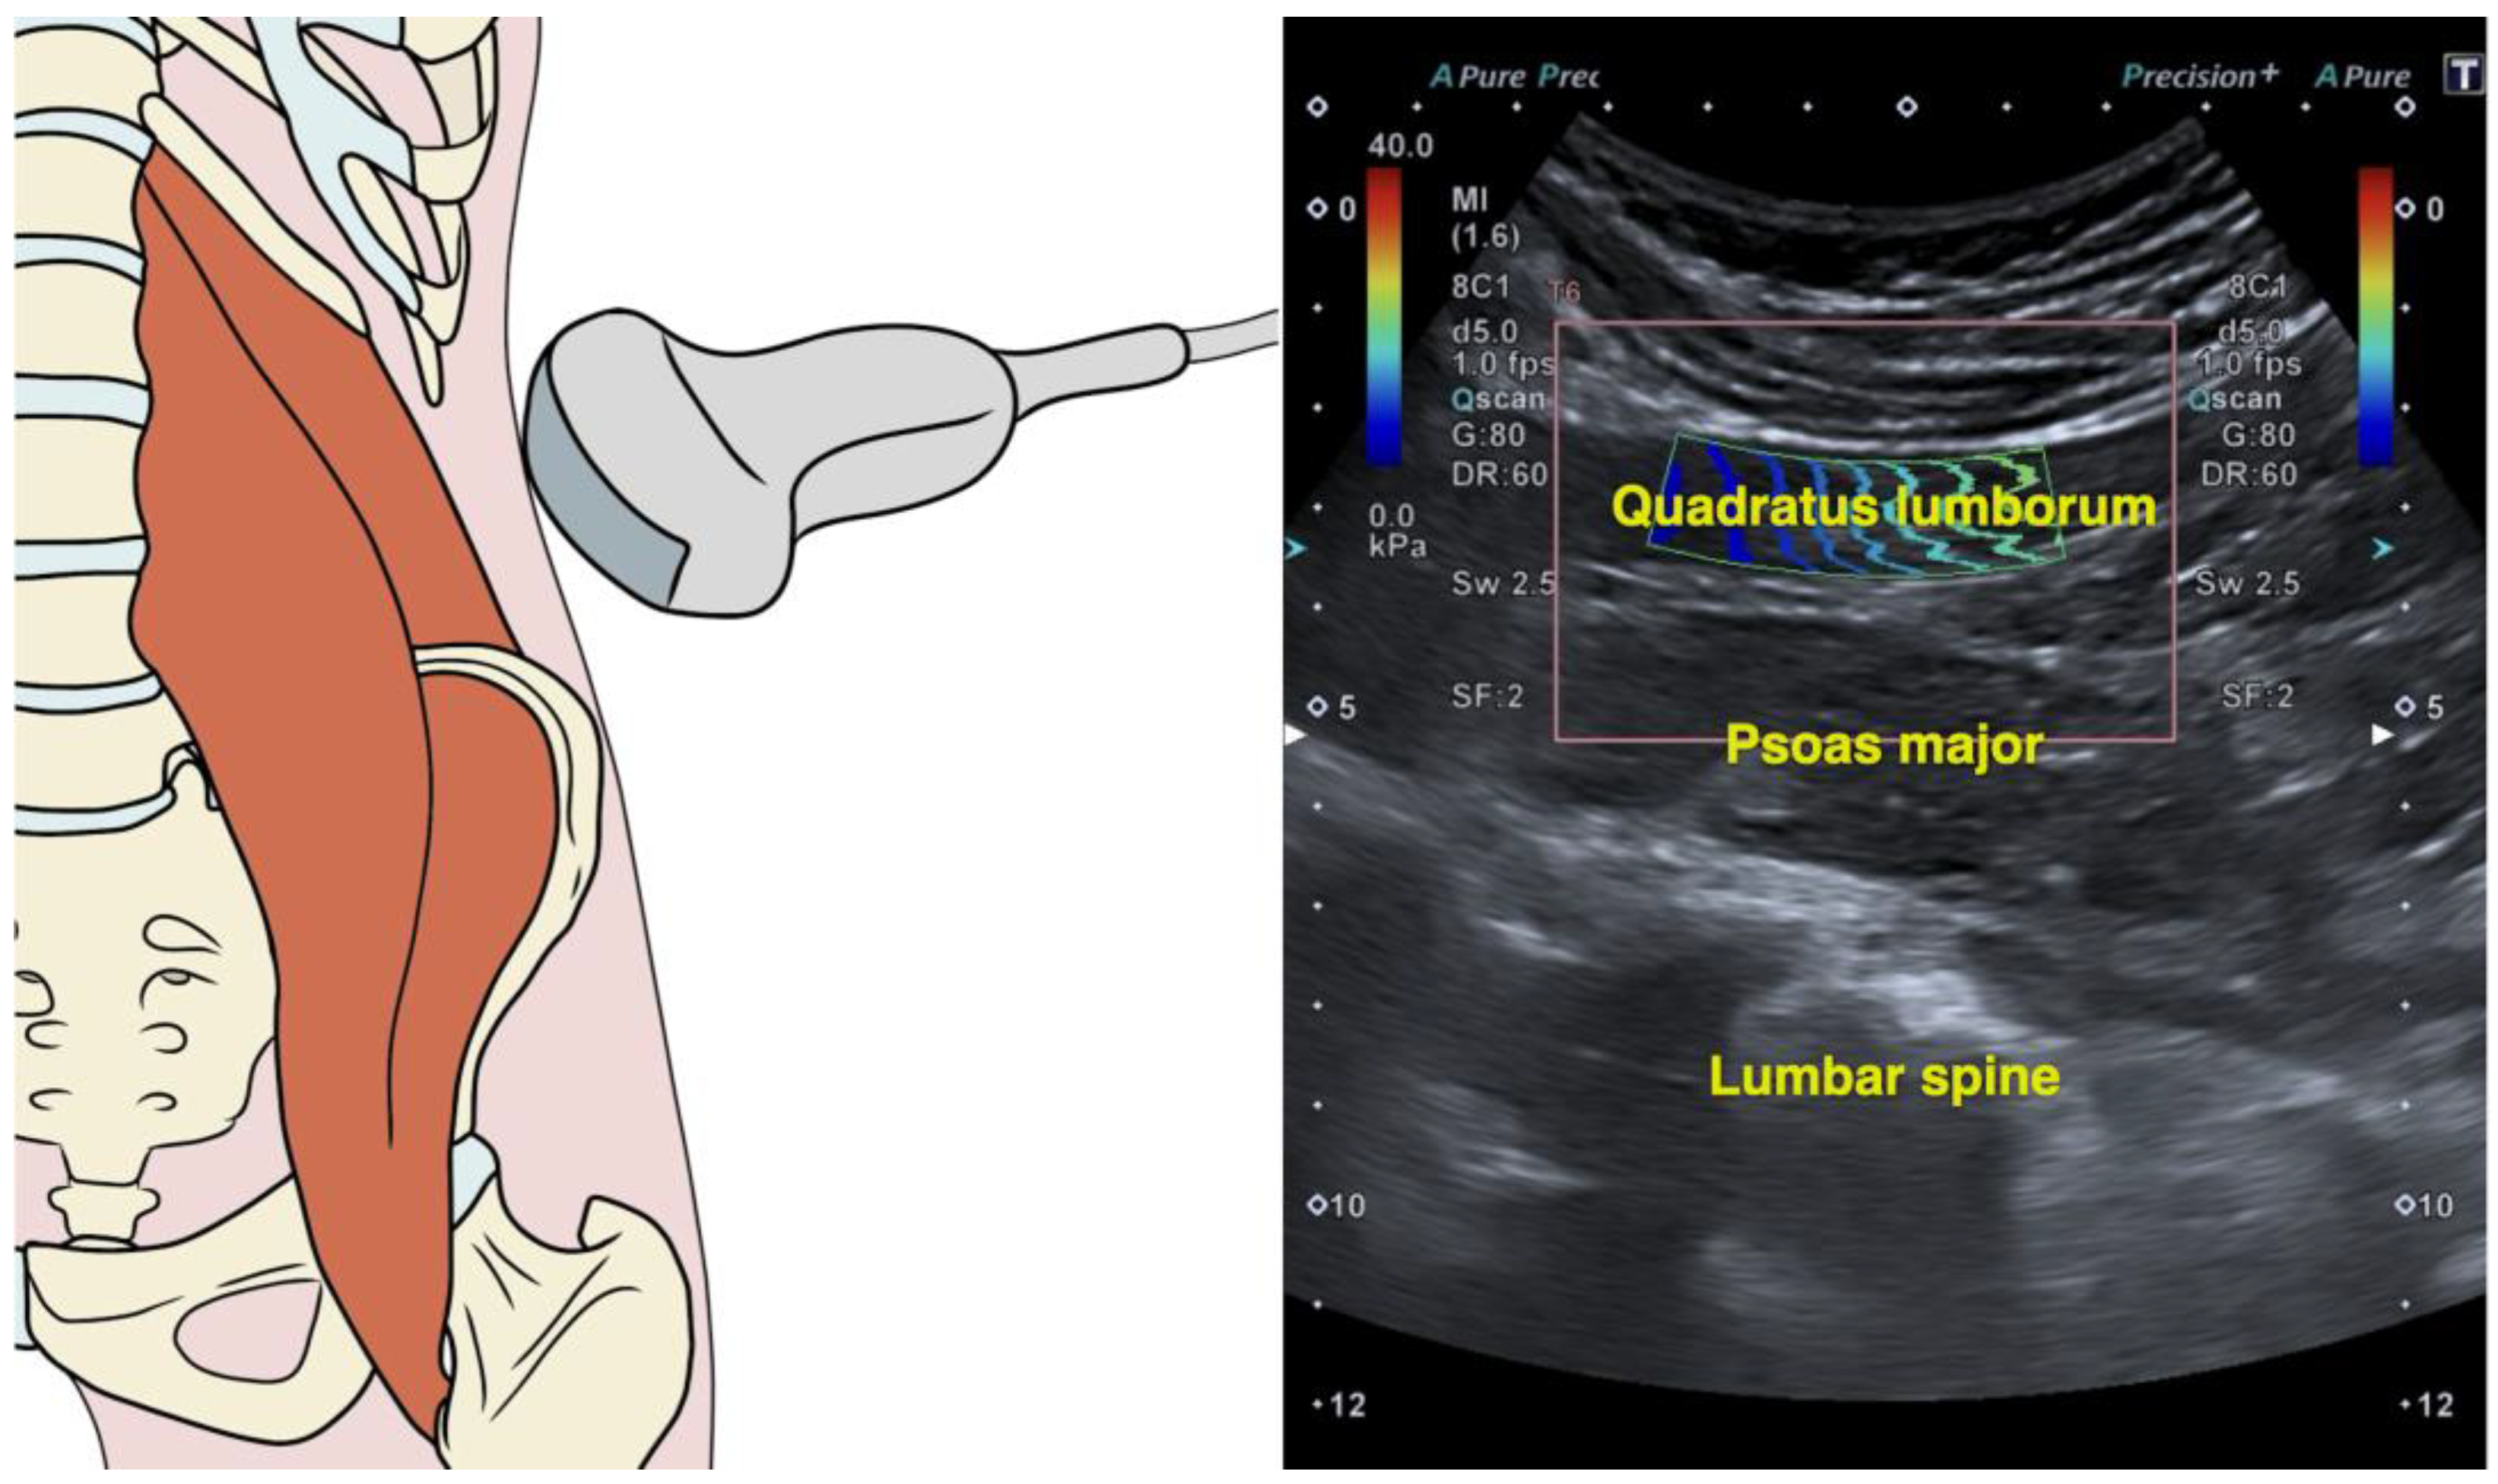

2.4. Quadratus Lumborum Muscle Stiffness

- Zhou, E.F.M.; Wong, A.Y.L.; Zheng, Y.P.; Lam, K.H.S.; Fu, S.N. Reliability of Ultrasound Shear Wave Elastography for Evaluating Psoas Major and Quadratus Lumborum Stiffness: Gender and Physical Activity Effects. Ultrasound Med. Biol. 2024, 50, 564–570. [Google Scholar] [CrossRef] [PubMed]